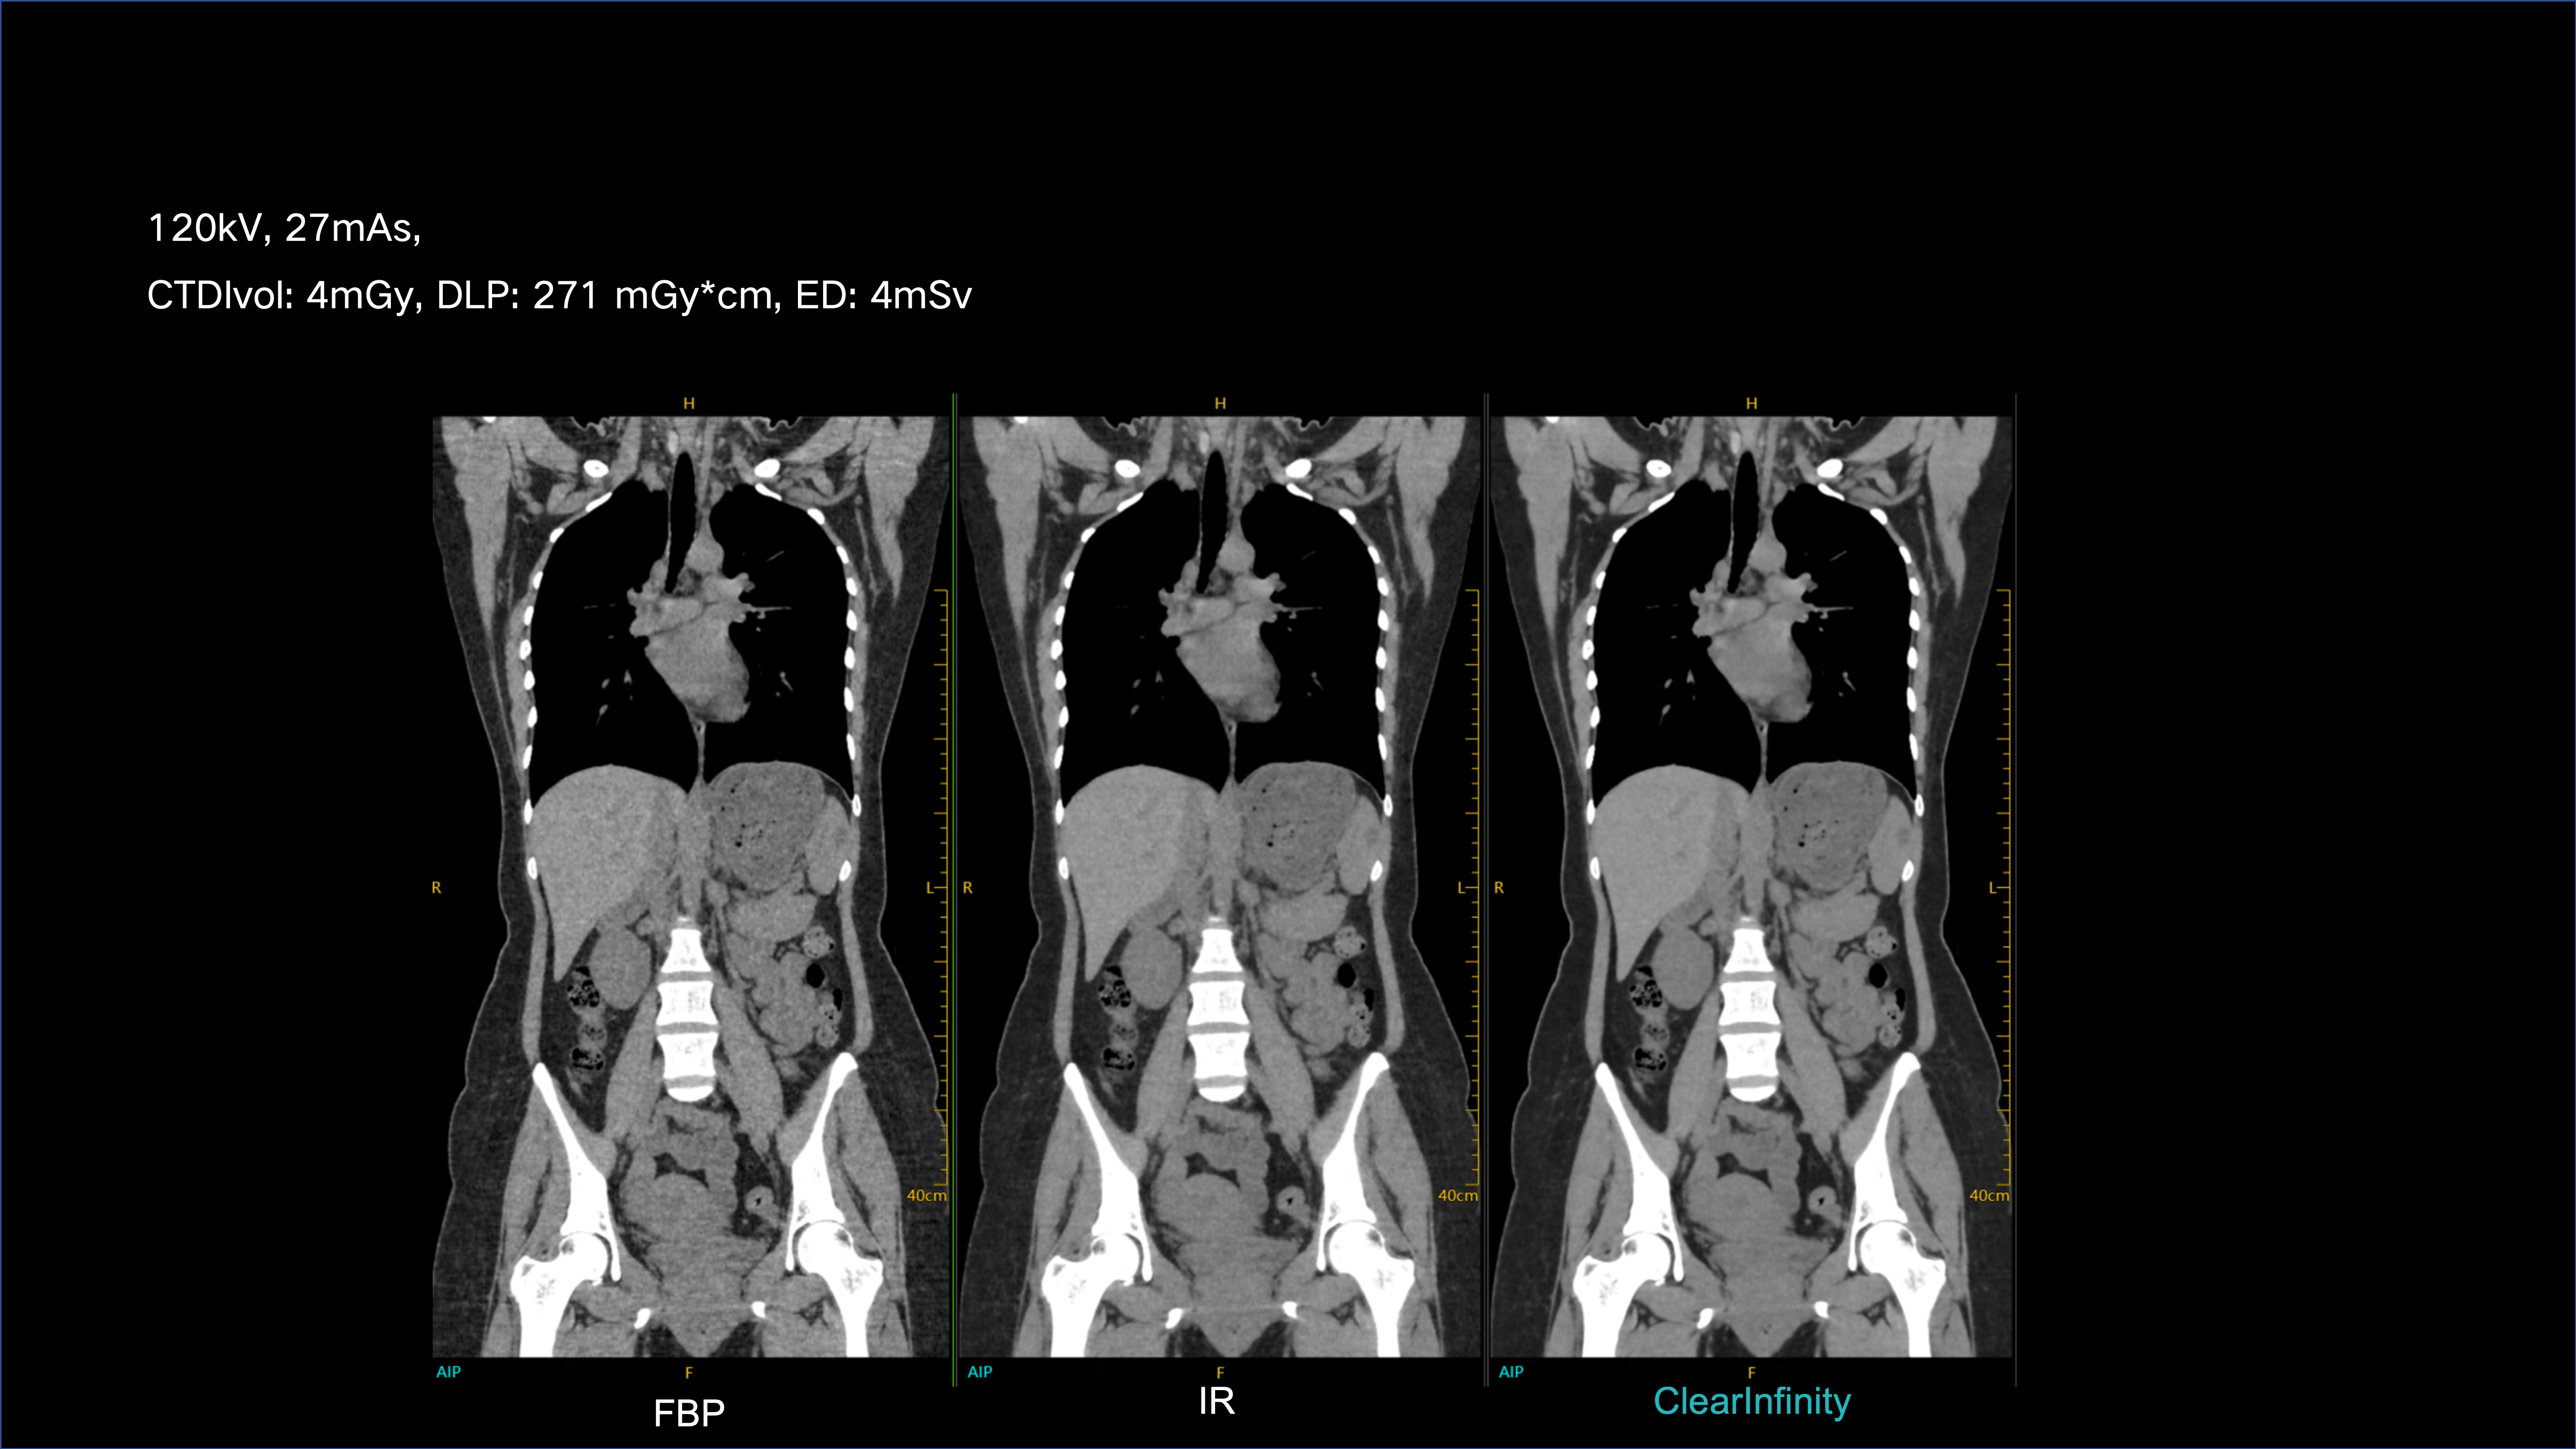

ClearInfinity AI preserves natural texture while ensuring ultra-low-dose clarity.

Delivers extraordinary spatial detail for confident, accurate diagnosis.